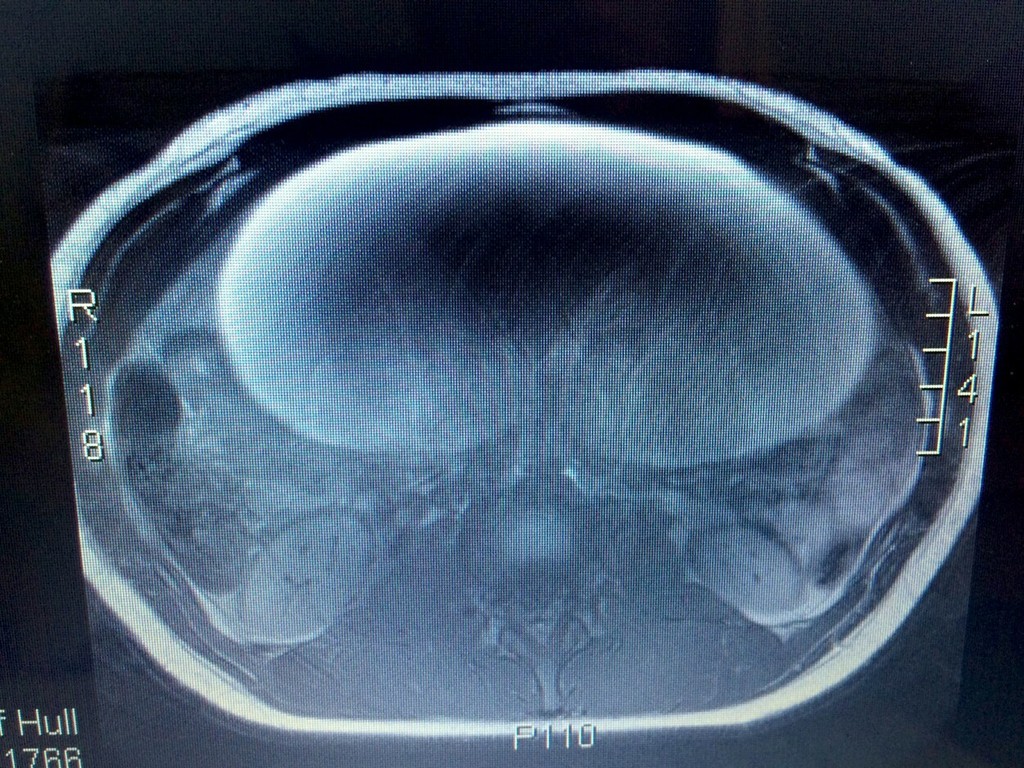

Olivia mala na vaječníku tumor, ktorý vážil takmer 10 kilogramov.

Sedemnásťročná študentka Olivia Key skutočne vyzerala ako tehotná. Keď ju priviezli do nemocnice s obrovskými bolesťami v bruchu, mysleli si to aj lekári. Ale tehotenské brucho sa po vyšetrení zmenilo na niečo strašné. Olivia mala na vaječníku tumor, ktorý vážil takmer 10 kilogramov.

Mladé dievča pochádzajúce z Hullu si všimlo, že má nafúknuté brucho počas leta 2013, ale ignorovalo to. Pokiaľ neprišli hrozné bolesti. Olivii urobili krvné testy, otestovali jej aj moč a vylúčili tiež zápal slepého čreva. Až keď jej urobili ultrazvuk prišli na to, čo je skutočnou príčinou bolesti.

"Nádor bol veľký ako melón a bola som zhrozená, že som také niečo mala v bruchu. Keď mi povedali, že je zhubný, ostala som šokovaná. Nikdy by som si nepomyslela, že mi v 17-tich rokoch pôjde o život," povedala Olivia pre The Sun.

Tínedžerke nádor vyoperovali. Našťastie sa rakovina nerozšírila do iných častí tela.